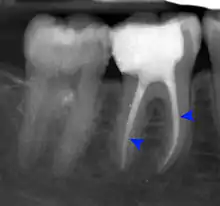

Apical abscess associated with roots of a lower molar.

Apical periodontitis is acute or chronic inflammation around the apex of a tooth caused by an immune response to bacteria within an infected pulp.[20] It does not occur because of pulp necrosis, meaning that a tooth that tests as if it's alive (vital) may cause apical periodontitis, and a pulp which has become non-vital due to a sterile, non-infectious processes (such as trauma) may not cause any apical periodontitis.[10]:225 Bacterial cytotoxins reach the region around the roots of the tooth via the apical foramina and lateral canals, causing vasodilation, sensitization of nerves, osteolysis (bone resorption) and potentially abscess or cyst formation.[10]:228

The periodontal ligament becomes inflamed and there may be pain when biting or tapping on the tooth. On an X-ray, bone resorption appears as a radiolucent area around the end of the root, although this does not manifest immediately.[10]:228 Acute apical periodontitis is characterized by well-localized, spontaneous, persistent, moderate to severe pain.[6]:125–135 The alveolar process may be tender to palpation over the roots. The tooth may be raised in the socket and feel more prominent than the adjacent teeth.[6]:125–135